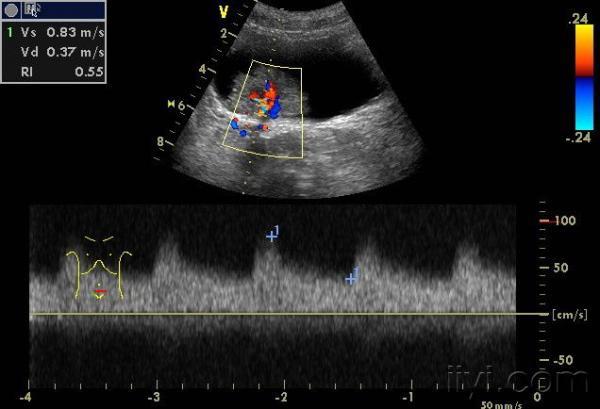

频谱呈高速血流